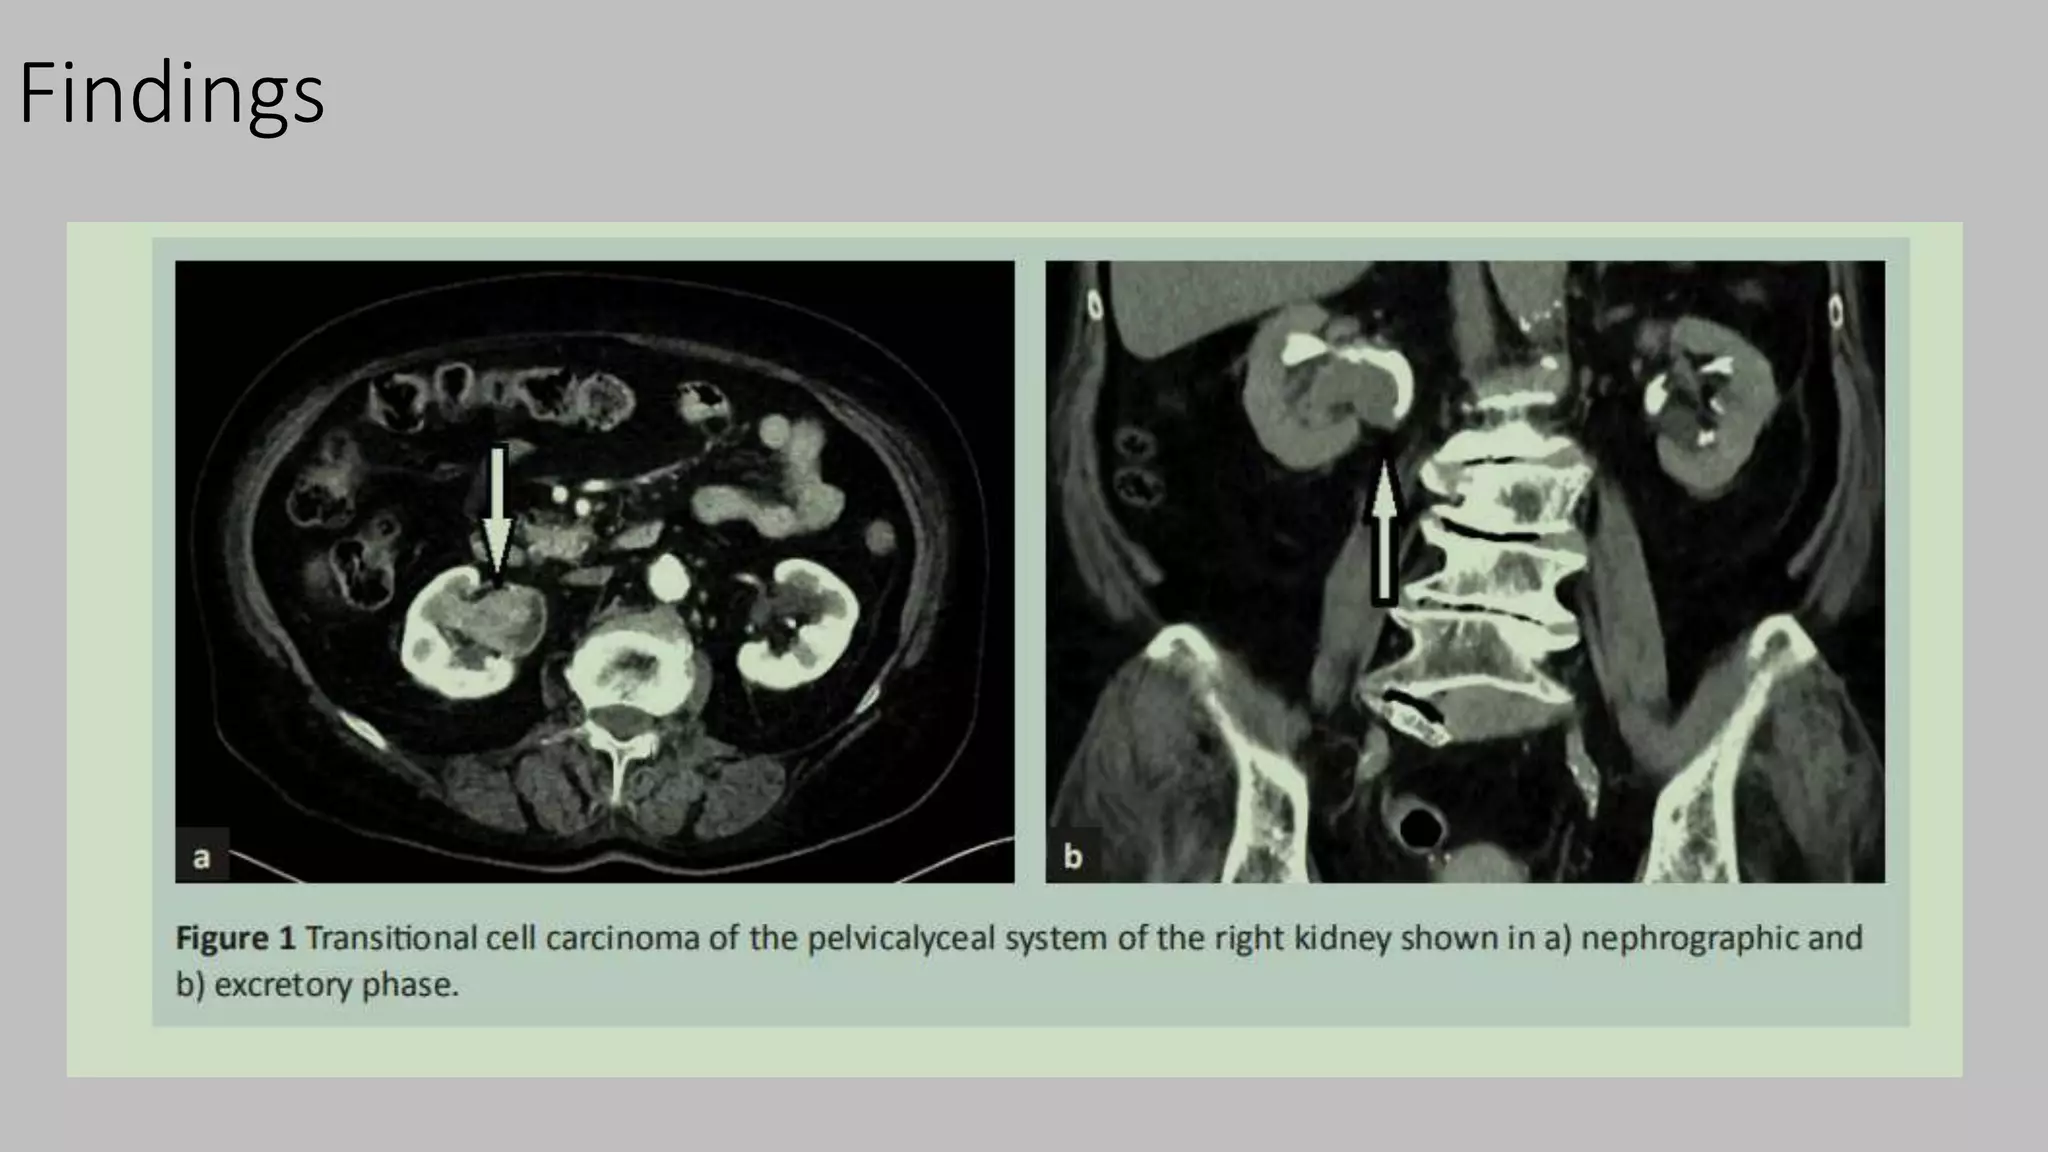

Findings

Contd..

Contd…